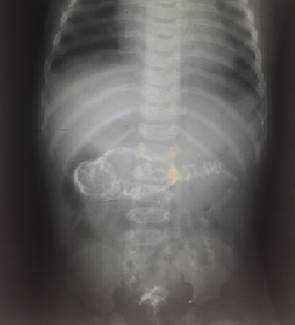

На рисунках 2 и 3 отображена ультразвуковая картина кишечной инвагинации.

Рис. 2. Симптом «мишени»

Рис. 3. Симптом «псевдопочки»